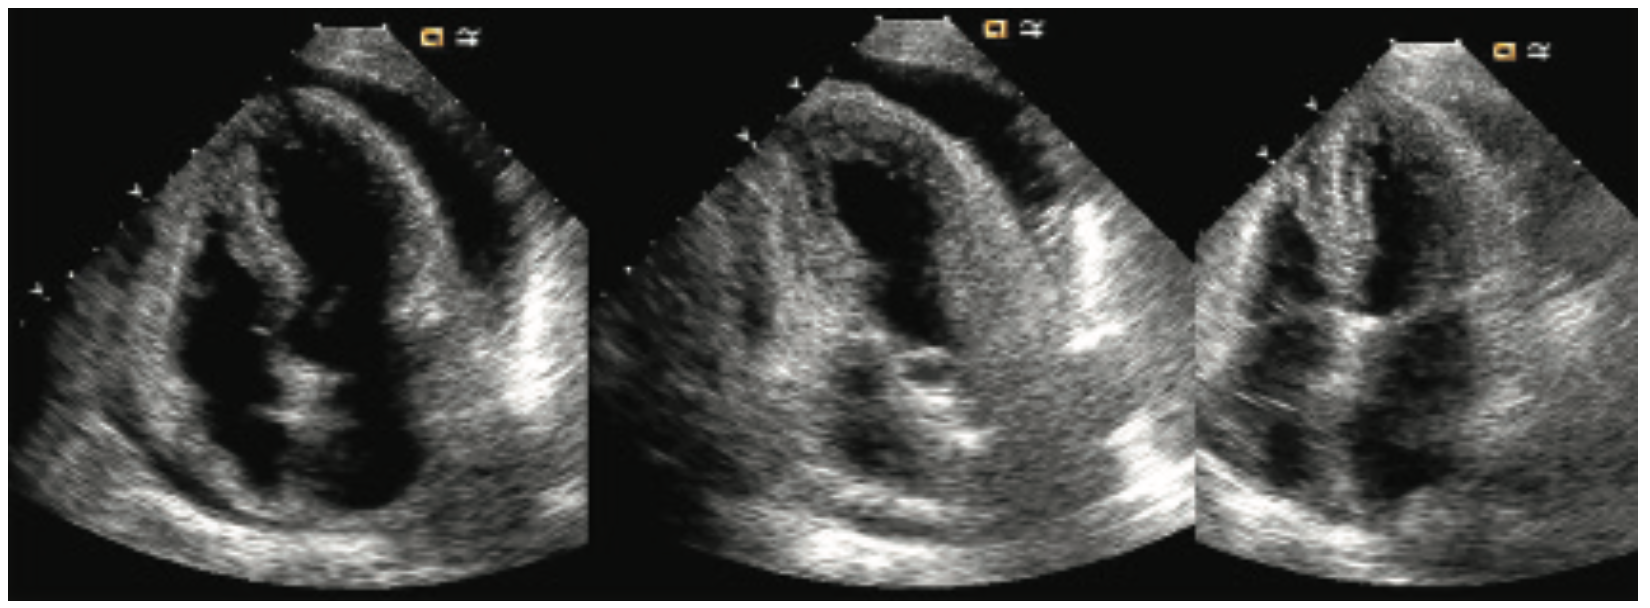

In another case illustrating tamponade after an LV gram or during a percutaneous coronary intervention (PCI) with wire perforation, the arterial pressure tracing (Figure 4) shows a narrowed pulse pressure, tachycardia, and large differences in systolic pressure variation between inspiration and expiration (pulsus paradoxus), typical hemodynamic findings for pericardial tamponade. Noting such a pressure, the operators should prepare to perform immediate pericardiocentesis, begin fluid resuscitation, and notify the operating room as the situation requires. An in-lab echo is very helpful in identifying the fluid and assisting in the pericardiocentesis. Figure 5 shows echocardiographic frames of the effusion, bubble contrast during pericardiocentesis image, and a post-cath evacuation of the pericardial fluid.

The hemodynamics before pericardiocentesis show arterial pressure pulsus paradoxus with a mean arterial pressure of 110 mmHg (Figure 6). The middle frame shows elevated right atrial and pericardial pressures. In this case, although RA/pericardial pressures are not identical, the blunted pressure waveforms and near-mean equalization at around 22 mmHg are consistent with the echo findings. After pericardiocentesis, arterial pulse pressure and respiratory variations have resolved with an increase in mean arterial pressure and decrease in RA pressure. The final RA pressure at 12 mmHg suggests some effusive-constrictive pericardiocentesis remains.